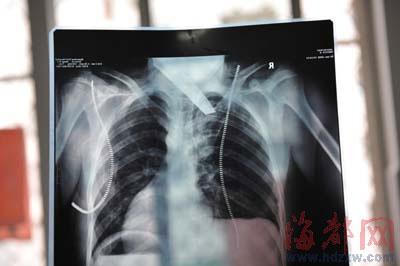

前晚,在第一醫(yī)院急救室,經(jīng)過(guò)4個(gè)多小時(shí)的搶救,醫(yī)生將匕首從小勇身上取出,發(fā)現(xiàn)這把匕首的刀尖扎斷了1厘米。由于小勇肺部被刺中,昨天上午,醫(yī)生再次進(jìn)行了3個(gè)多小時(shí)的手術(shù),切除了受傷的部分肺,直到下午,小勇才挺過(guò)來(lái)。“挺了一夜,現(xiàn)在總算醒了過(guò)來(lái)。”楊女士一夜沒(méi)睡,守在手術(shù)室外7個(gè)多小時(shí),生怕兒子再醒不過(guò)來(lái)。不過(guò),由于傷勢(shì)嚴(yán)重,小勇目前戴著氧氣呼吸,仍未脫險(xiǎn)。